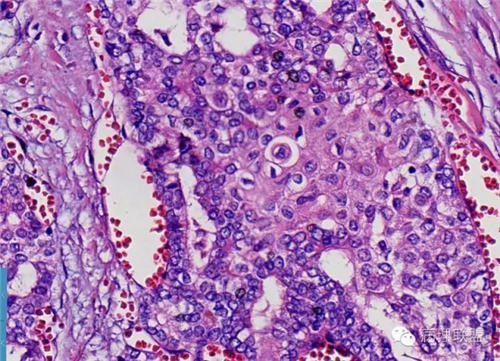

肺的

不仅仅是肺水肿

各种各样……